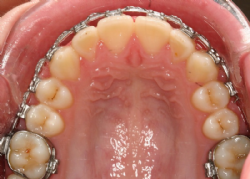

Festsitzende Apparaturen werden hauptsächlich im bleibenden Gebiss zur Behandlung von Fehlstellungen benutzt, also bei Jugendlichen und Erwachsenen. Aber auch im Wechselgebiss werden häufig festsitzende Elemente mit herausnehmbaren Apparaturen kombiniert.

- Fast jede Zahnfehlstellung ist mittels festsitzender Zahnspange korrigierbar.

- Behandlungszeit ist kürzer als bei herausnehmbaren Apparaturen, da das Gerät 24h am Tag wirken kann.